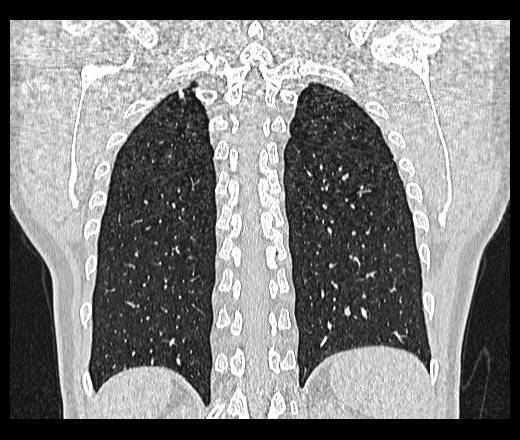

Как очаги в легких выглядят на снимке КТ?

Чтобы человек несведущий смог разобраться в результатах КТ, следует знать о нюансах чтения снимков. Рассмотрим самые актуальные:

- Очаговые образования представляют собой участки белого цвета на черном фоне (на снимке-негативе). В реальности пораженная область, скорее всего, имеет более темный цвет, чем здоровые ткани легкого.

- Если врач заметит на снимке участки кальцинирования или обызвествления (капсул, пропитанных солями кальция) вокруг очага, это может быть признаком доброкачественности образования. Кальцинаты по цвету похожи на кости скелета, видимые на этом снимке. Такие явления часто обнаруживаются после затяжных простудных заболеваний, бронхитов или уже излечененного туберкулеза и представляют собой некий шрам на легких. Пациента с образованием, на котором заметны признаки кальцината, пульмонологи обычно просят раз в полгода делать контрольные снимки.

- В случае, когда образование представляет собой так называемое «облачко» или очаг по типу «матового стекла», требуется более предметное обследование. Внешне оно выглядит как затуманенная область с размытыми границами. В ряде стран пациентам с такими образованиями сразу рекомендуется операция, даже если оно не растет. Уже доказано, что в 80% случаев такие очаги являются предраковым состоянием легких. Альтернатива немедленной операции — постоянное наблюдение с контрольными снимками раз в полгода-год.